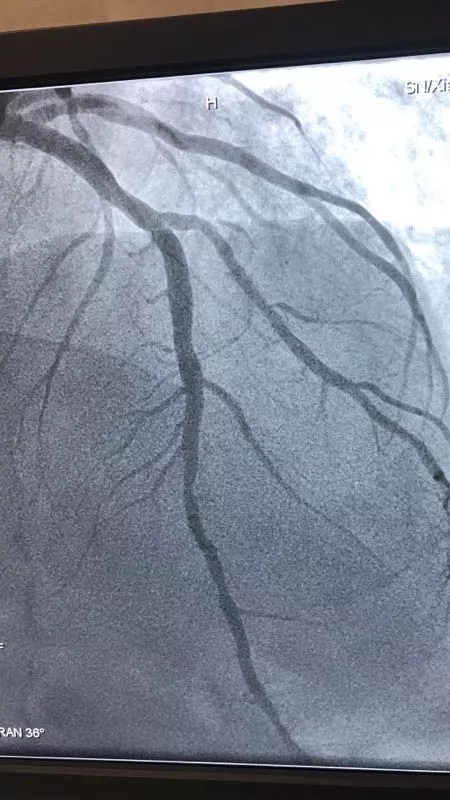

CCU病区成功实施冠脉药物涂层球囊扩张术 治疗支架内再狭窄